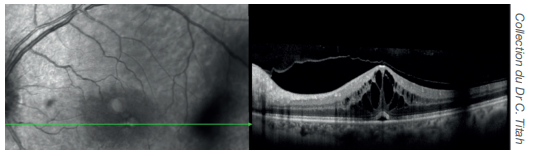

Œdème maculaire

Image en OCT - angiographie